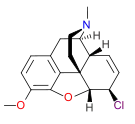

Morphides

- α-Chlorocodide (= chlorocodide)

- β-Chlorocodide

- α-Chloromorphide (= chloromorphide)

- Bromocodide

- Bromomorphide

- Chlorodihydrocodide

- Chloromorphide

- Codide

Structures

| Morphides | ||||

|---|---|---|---|---|

α-chlorocodide α-chlorocodide |

β-chlorocodide β-chlorocodide |

Bromomorphide Bromomorphide | ||

Chlorodihydrocodide. Chlorodihydrocodide. |

Chloromorphide Chloromorphide |

Codide Codide | ||